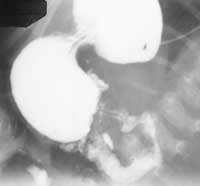

Признаком, свидетельствующим о сужении пилорического канала не только вследствие гипертрофии мышц, но и утолщения слизистой оболочки, является «симптом параллельных линий», образованных значительно расширенными складками слизистой оболочки. При получении изображения всего удлиненного пилорического канала наблюдается различная степень заполнения луковицы двенадцатиперстной кишки, в основании которой имеются вдавления от гипертрофированного мышечного слоя привратника в виде полумесяца (Рис. 3).

[Увеличить]

Рис. 3. Больной Г., 1,5 мес. Врожденный пилоростеноз. Симптом «параллельных линий». Распределение контраста по тонкой кишке мелкими порциями.